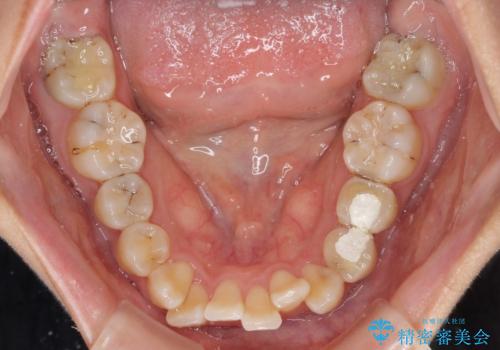

- 虫歯が多く、磨きにくい歯並びを改善したいとのことで来院された患者様です。

歯列は叢生が認められる程度でしたが、やや前突感があったので、少しでも口が閉じやすくなるように仕上げる方針としました。

神経を取り除かれている歯3本以外にも虫歯が認められたため、事前に処置を行い、インビザラインにて矯正治療を行うこととしました。